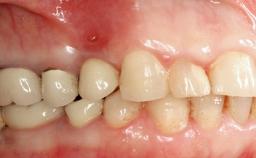

A 24-year-old female patient was treated with an implant- supported crown for single-tooth replacement at site 11. A Straumann Bone Level RC implant (Institut Straumann AG, Basel, Switzerland) was placed with simultaneous bone augmentation, and the periimplant emergence profile was conditioned with a fixed implant-supported provisional crown. After finalization of the mucosal architecture, the clinical situation was transferred by means of a custom impression post for fabrication of an implant-supported screw-retained onepiece crown consisting of a CARES® zirconia abutment (Straumann) with a direct ceramic veneer.